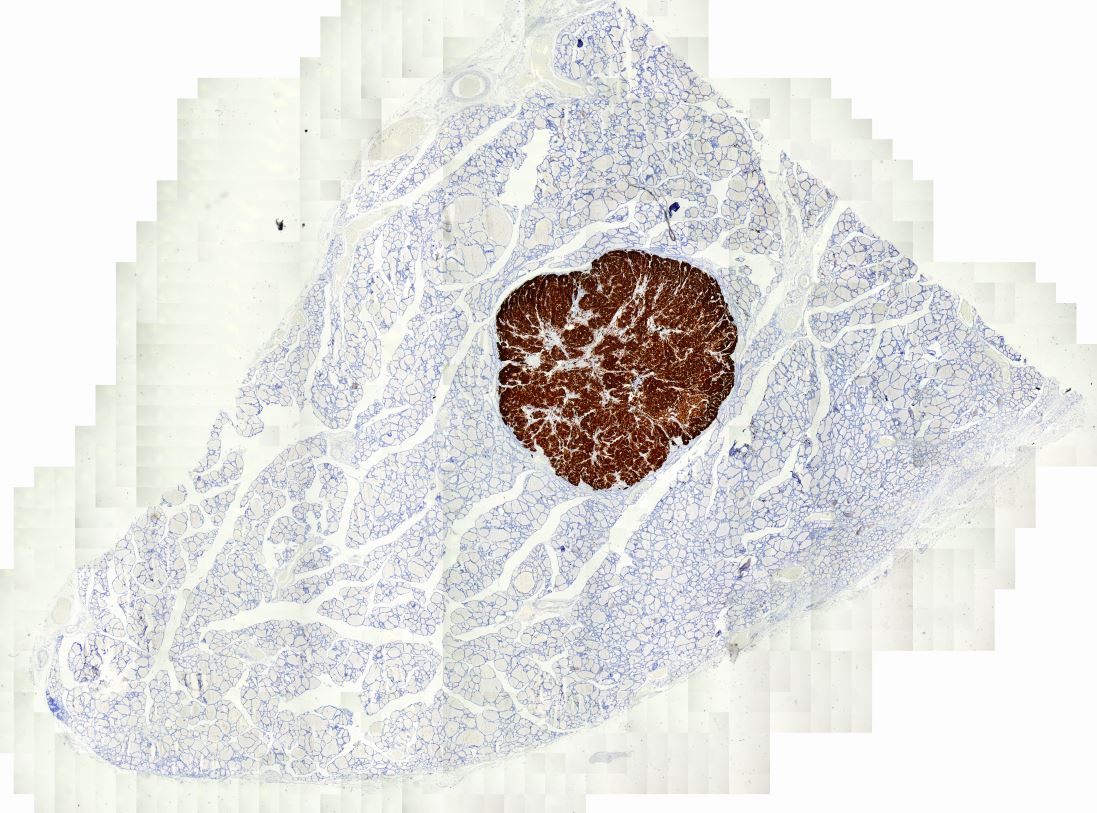

Cribriform-morular thyroid carcinoma Tiroidin nadir tümörü. Belirsiz papiller yapılar, moruller ve tiroglobulin yokluğu. Beta katanin ilişkili.

Tiroglobulin, Cribriform-morular thyroid carcinoma Tiroglobulin negatifliği olan tiroid tümörü

Cribriform-morular thyroid carcinoma, ikinci odak ile birlikte Çok sayıda odak içeren tümörde iki ayrı tümör odağı

Beta-Catenin pozitifliği, Cribriform-morular thyroid carcinoma Beta-Catenin nükleer ve sitoplazmik pozitiflik.

ER pozitifliği, Cribriform-morular thyroid carcinoma ER hormon reseptöründe yaygın pozitiflik. Tiroid için beklenmeyen özellik.

Morul yapılarındaCD10 pozitifliği, Cribriform-morular thyroid carcinoma Cribriform-morular thyroid carcinoma morul yapıkarını boyayan markerlardan biri.